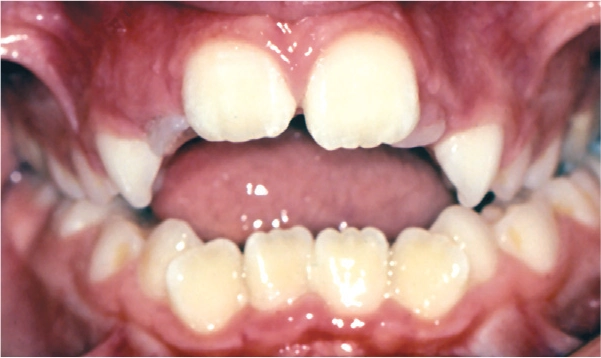

Open Bite

Malocclusions, like those illustrated above, may benefit from early diagnosis through full orthodontic examination.